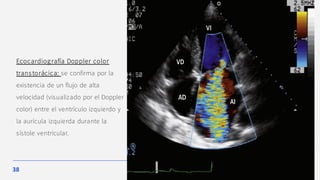

Ecocardiograma

Los datos morfológicos de la válvula mitral permiten diferenciar entre los

distintos mecanismos y sospechar una determinada etiología.

El ecocardiograma Doppler es la técnica de elección para confirmar el

diagnóstico y para valorar la etiología y la gravedad, así como el estado de la

función ventricular.

El diagnós tico por Doppler color se bas a en la detección de un flujo

turbulento en la aurícula izquierda durante la sístole.

Ecocardiografía Doppler color

transtorácica: se confirma por la

existencia de un flujo de alta

velocidad (visualizado por el Doppler

color) entre el ventrículo izquierdo y

la aurícula izquierda durante la

sístole ventricular.